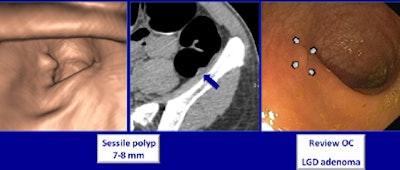

VC did well, and so did the teleradiology scheme. Compared with conventional optical colonoscopy, CTC showed sensitivities in the high 90s, well above those of conventional optical colonoscopy, according to a presentation at the recent RSNA 2011 meeting in Chicago. In addition, CTC had far fewer false positives compared with optical colonoscopy.

In all, nine patients had areas of nontagged stool (1.8%), and three patients had segments with poor distention (0.6%). All files were successfully transmitted. CTC and optical colonoscopy revealed 88 polyps that were 6 mm or larger in 69 patients, the team found.

Based on results from both exams, including repeated colonoscopy exams when necessary, CTC actually beat out optical colonoscopy in two areas: Sensitivity for detecting adenomas 6 mm and larger was 98% sensitivity for CTC versus 90% for optical colonoscopy, and sensitivity for detecting advanced neoplasia was 100% for CTC versus 91% for colonoscopy. The calculation takes into account six missed lesions plus 14 lesions confirmed at repeat CTC -- 14 of the 20 lesions that colonoscopy missed were in the right colon, where colonoscopy has traditionally done a poorer job.